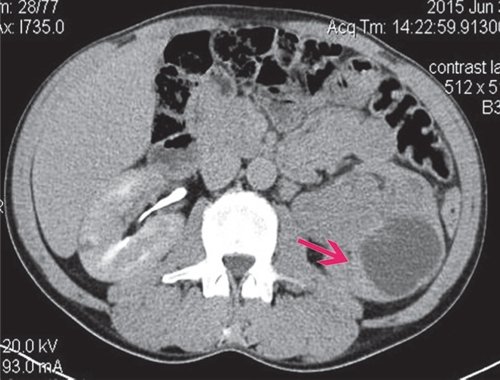

При КТ в нижне-средних отделах ЧЛС справа определяется мягкотканное объемное образование с четкими контурами размером 50×40 мм, деформирующее ЧЛС, фрагментарно накапливает контрастное вещество (рис. 10).

а) Нативная фаза. В нижне-средних отделах ЧЛС справа мягкотканное объемное образование с четкими контурами размером 50×40 мм, деформирующее ЧЛС.

б) Артериальная фаза. Образование неравномерно накапливает контрастное вещество.

в) Отсроченная фаза. Фрагментарные признаки дефекта наполнения чашечек.